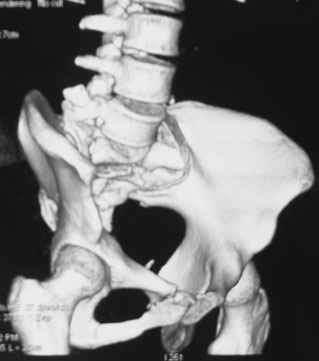

Травма 21.августа 2005г. На девочку в лесу упала береза. Доставлена в ближайшую ЦРБ. При поступлении установлен диагноз: Травматический шок 2-3 ст. Тупая травма живота. Забрюшинная гематома. Перелом костей таза с нарушением целостности тазового кольца. Перелом лонной и седалищной костей справа. Перелом поперечных отростков L3 - L5. Разрыв КПС справа. При поступлении выполнена диагностическая лапароскопия — выявлена обширная забрюшинная гематома. Было наложено скелетное вытяжение за бугристости обеих б/берцовых костей, больная уложена в гамак. Через неделю скелетное вытяжение демонтировано, гамак снят. Девочка уложена в положение «лягушки». Контрольные рентгенограммы через 4 недели после травмы. Заподозрен перелом дужки L5. Больная 26 сентября 2005 г. переведена в областную больницу в отделение детской ортопедии. При поступлении в локальном статусе: пальпация и перкуссия остистых и поперечных отростков L4-5 болезненная. Пальпация костей таза б/болезненная. С-м натяжения слабо положителен. Осевая нагрузка положительная. Движения в т/б суставах ограничены, болезненны. C-м прилипшей пятки отрицательный. C-м Ларрея и Варнейля отрицательный. Периферическая гемодинамика не нарушена.Неврологический статус: вторичная двусторонняя радикулопатия L5-S1. 29 сентября произведена компьютерная томография позвоночника и таза.

Судя по томограммам, радикулопатия может быть из-за компресии "конского хвоста" смещенным крестцовым позвонком, это хорошо видно на втором слева снимке. Если этот сегмент будет нестабилен и будет сохраняться неврологическая симптоматика, придется оперировать. Если неврологическая симптоматика уйдет и перелом стабилизируется, то можно обойтись без операции.